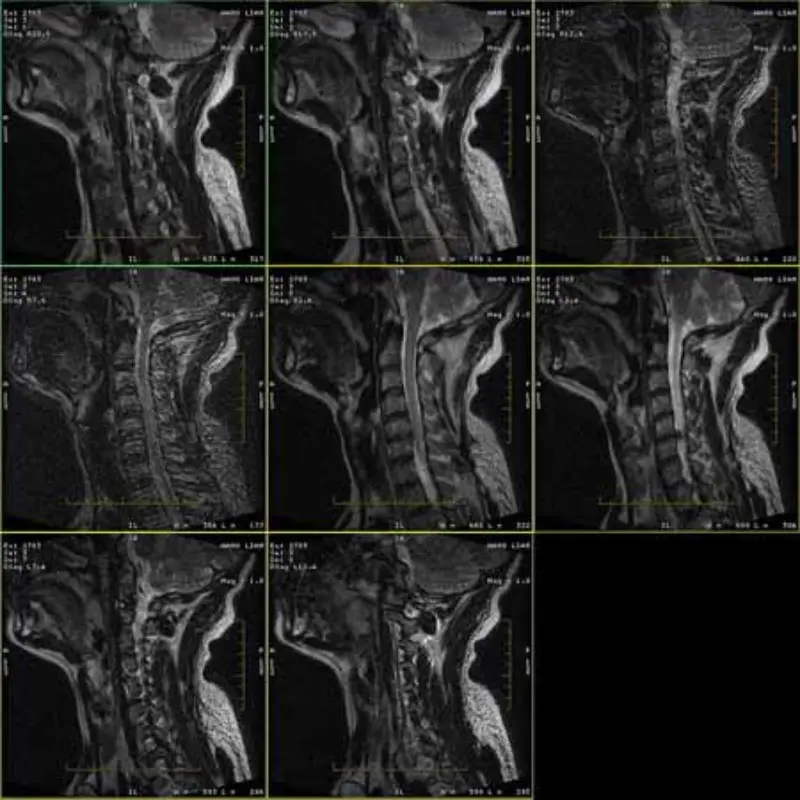

FRFSE ja GRE protokollide piltidel on kummitus ja mõnikord ilmuvad madala SNR-i kujutised ühes seerias. Kuid SE protokolli pildid on normaalsed.

Palun vaadake lisatud pilte.